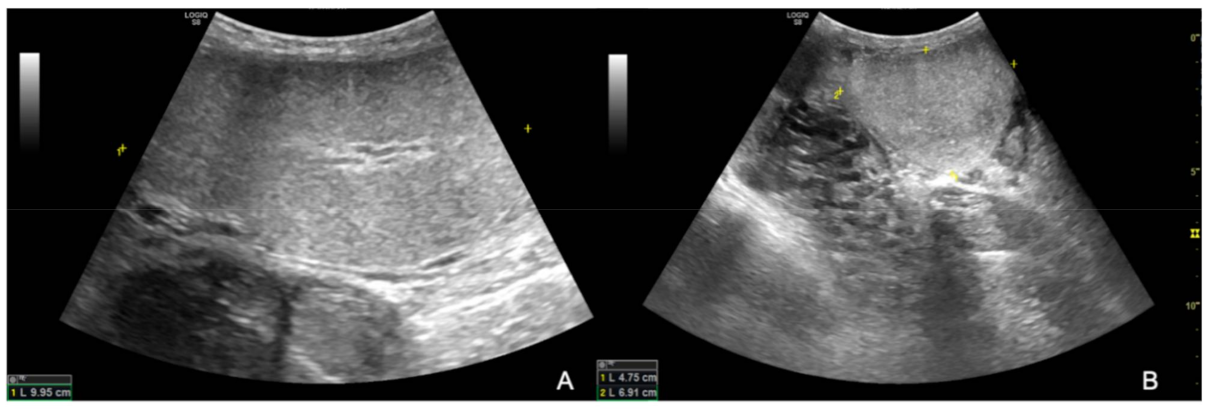

The ultrasound examination showed that the right testicle appeared normal (Figure 2), while the left testicle severely enlarged (13.35 cm CrCd × 8.19 cm DV × 9.42 cm LL vs. 9.25 cm CrCd × 4.75 cm DV × 6.91 cm LL). The parenchyma was characterized by the presence of multiple coalescing, nodular, well-defined and heterogeneous lesions of various size that almost completely effaced the normal anatomy and deformed the capsule or distorted normal shape (Figure 3); color Doppler and B-Flow evidenced a diffuse increase in vascularization, characterized by vessels of different size and localized both peripherally and in the central portion of the various nodular lesions, instead of normal unform vessel distribution from the capsule to the testicle mediastinum (Figure 4).

Figure 2. B-mode longitudinal (A) and transverse (B) images of the right testicle; note the homogeneous appearance of normal testicular parenchyma.

Figure 3. B-mode longitudinal (A) and transverse (B) images of the left testicle; the black arrows point at the heterogeneous and well-defined nodular lesions effacing the normal testicular parenchyma.